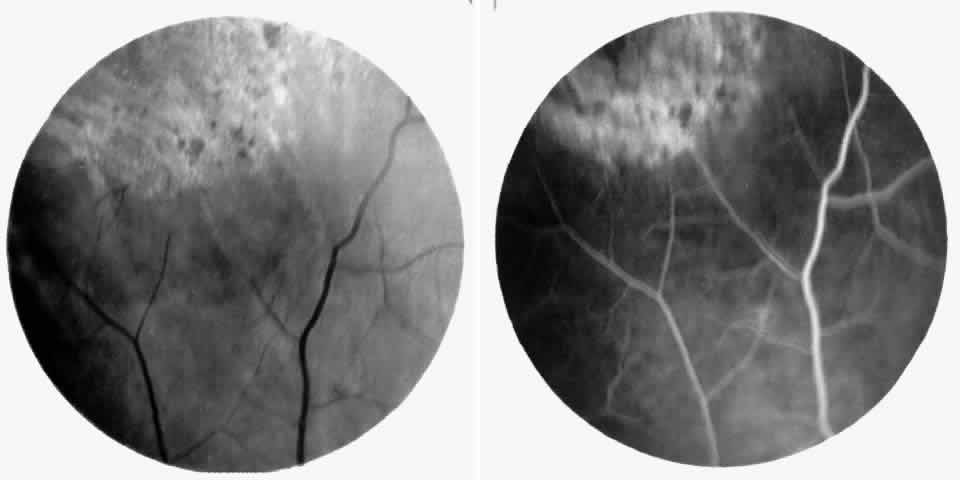

Vascular Tortuosity

Dilation and tortuosity of the retinal veins was one of the first recognized abnormalities of sickle cell eye disease. Although it is not pathognomonic of sickle cell disease, it reportedly occurs in up to 47% of patients with homozygous sickle cell anemia and 32% of patients with SC disease (Fig. 4).70 The significance of this venous tortuosity is unknown, and the incidence does not appear to be related to age.71

Fig. 4. A. Generalized vascular tortuosity, predominantly venous, in a patient with homozygous sickle cell anemia. B. Localized macular venous tortuosity in a patient with SC disease.